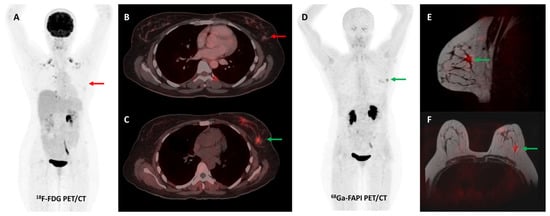

Loktev et al. conducted a proof-of-concept study in 2018 where they first demonstrated high lesional tracer uptake in three patients with breast, lung, and pancreatic cancers on FAPI PET imaging [24]. Subsequently, the same group from Heidelberg reported [68Ga]Ga-FAPI-04 PET/CT results of 80 patients with 28 different tumor types. The degree of tracer uptake differed significantly among tumor types, being highest in sarcoma, cholangiocarcinoma, esophageal, breast, and lung cancer [51]. Few other basket trials evaluated FAPI PET/CT in heterogeneous, oncological patient cohorts. The most consistent advantage of FAPI over FDG across these studies was easier lesion detection owing to a significantly lower background signal, with resultant higher target-to-background ratios (TBRs) and sharp image contrast [52]. One such example is presented in Figure 2.

Figure 2.

[68Ga]Ga-FAPI-04 and FDG PET/CT images in a 59-year-old woman with biopsy-proven metastatic left lung adenocarcinoma. [68Ga]Ga-FAPI-04 PET/CT images revealed intensely tracer avid left hilar mass lesion ((B)—green arrow), multiple enlarged mediastinal ((A,C)—green arrows) lymph nodes, and bilateral adrenal metastases ((A,D)—green arrows depicting left adrenal lesion). Additionally, moderate left-sided pleural effusion with associated left lung lower lobe collapse was noted. Overall, FAPI PET/CT demonstrated higher tracer avidity and TBRs than FDG PET/CT ((E–H)—red arrows).